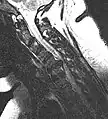

Herniated disc at C6–C7 level

Cervical disc herniations occur in the neck, most often between the fifth and sixth (C5–6) and the sixth and seventh (C6–7) cervical vertebral bodies. There is an increased susceptibility amongst older (60+) patients to herniations higher in the neck, especially at C3–4.[23] Symptoms of cervical herniations may be felt in the back of the skull, the neck, shoulder girdle, scapula, arm, and hand.[24] The nerves of the cervical plexus and brachial plexus can be affected.[25]

• Magnetic resonance imaging is the gold standard study for confirming a suspected LDH. With a diagnostic accuracy of 97%, it is the most sensitive study to visualize a herniated disc due to its significant ability in soft tissue visualization. MRI also has higher inter-observer reliability than other imaging modalities. It suggests disc herniation when it shows an increased T2-weighted signal at the posterior 10% of the disc. Degenerative disc diseases have shown a correlation with Modic type 1 changes. When evaluating for postoperative lumbar radiculopathies, the recommendation is that the MRI is performed with contrast unless otherwise contraindicated. MRI is more effective than CT in distinguishing inflammatory, malignant, or inflammatory etiologies of LDH. It is indicated relatively early in the course of evaluation (<8 weeks) when the patient presents with relative indications like significant pain, neurological motor deficits, and cauda equina syndrome. Diffusion tensor imaging is a type of MRI sequence used for detecting microstructural changes in the nerve root. It may be beneficial in understanding the changes that occur after herniated lumbar disc compresses a nerve root, and might help in differentiating the patients that need surgical intervention. In patients with a high suspicion of radiculopathy due to lumbar disc herniation, yet the MRI is equivocal or negative, nerve conduction studies are indicated.[44] T2-weighted images allow for clear visualization of protruded disc material in the spinal canal.